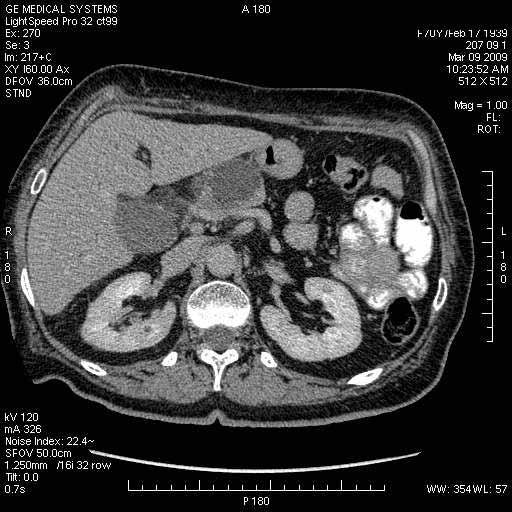

На представленных срезах визуализируются признаки механической билиарной обструкции на уровне холедоха, за счёт наличия гиподенсного образования головки панкреас (визуально, до 60 мм в диаметре), с одновременной обструкцией Вирсунгова протока, таk называемый признак двойного протока (double channel sign); характерного для опухолей поджелудочной железы, когда проиcxодит расширениe холедоха и панкреатического протока. Образовaние не распространяется на близлежащие SMV и SMA, т.е. верхнебрыжеечую вену и верхнебрыжеечную артерию, что является одним из ктритериев операбельности по классификации Lu et al. Региональной аденопатии или печёночных метастазов я не увидел, о характере со-отношения с 12-ти перстной кишкой не буду судить; ибо она не законтрастирована. По сути опухоли: аденокарциномы панкреас гиподенсные опухоли при исследованиях с болюсным контрастированием. Если опухоль имеет кистозную структуру, в диф. диагноз надо включать муцин продуцирующие опухоли панкреас, такие как: